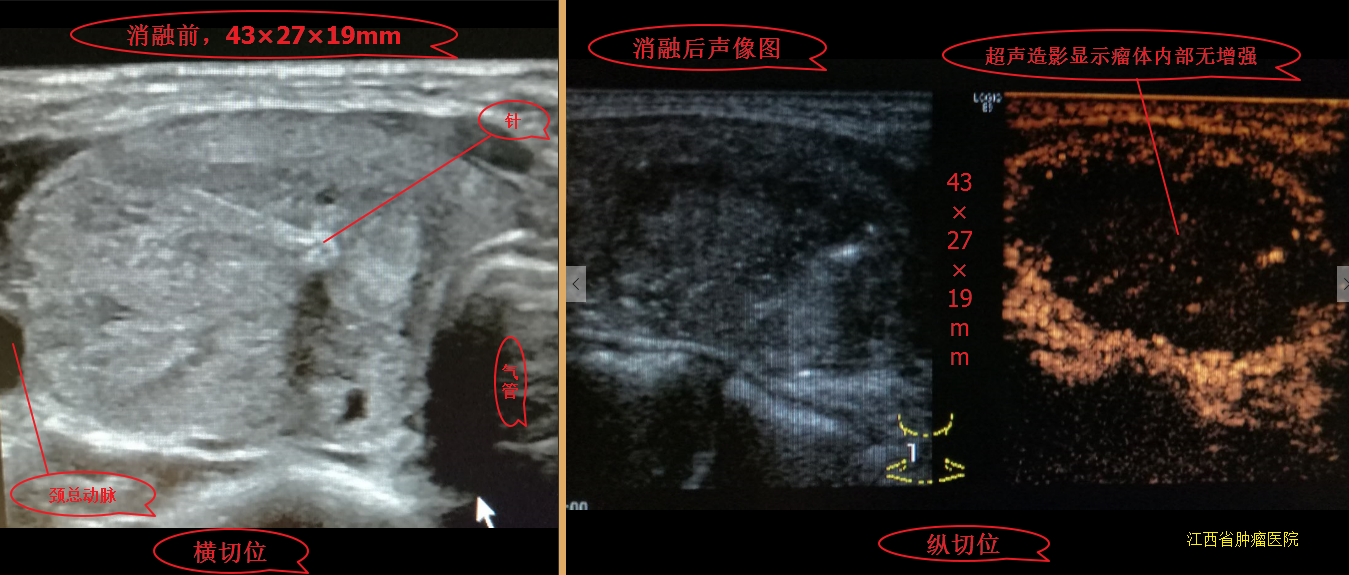

甲状腺结节微波消融术后,随访效果图! - 好大夫